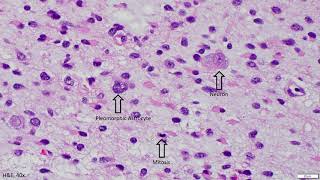

Glioblastoma histopathologic diagnosis Adventures in Neuropathology video

Glioblastoma histopathologic diagnosis - Adventures in Neuropathology

Glioblastoma histopathologic diagnosis - Adventures in Neuropathology Glioblastoma IDH Wildtype Histopathological Diagnosis